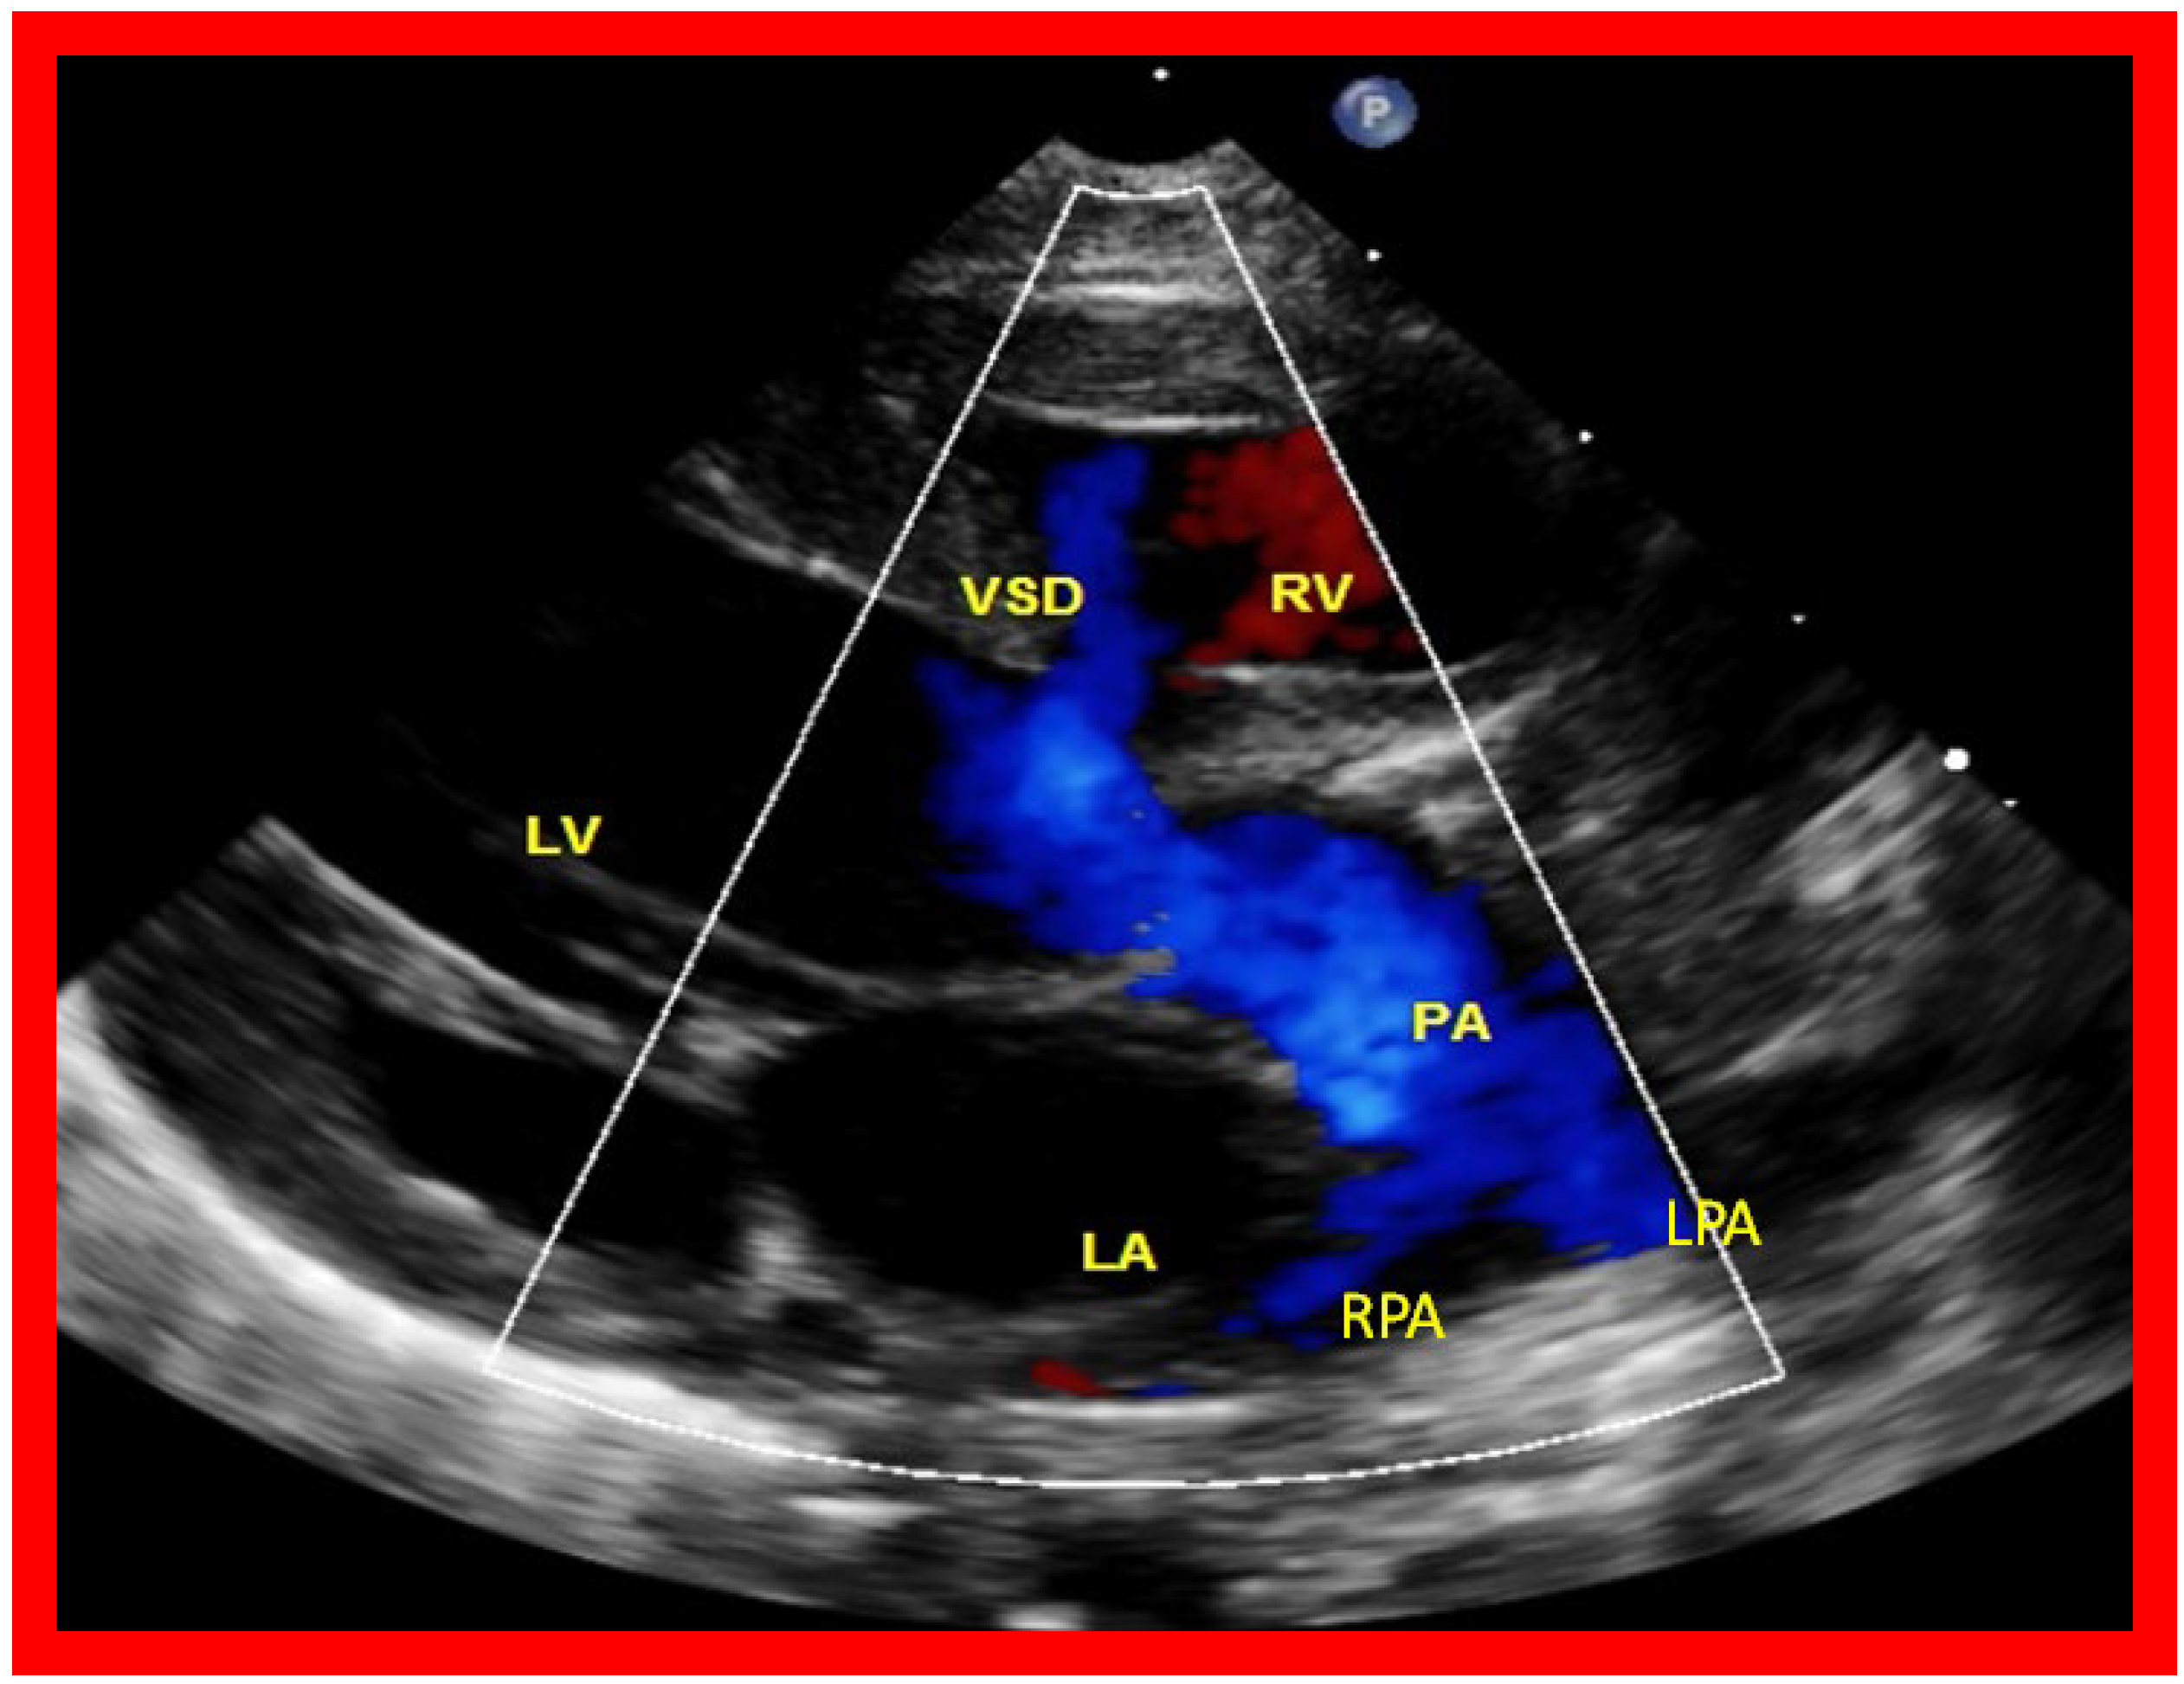

Then, the ventricular septum is evaluated; the ventricular septum is intact in most Type Ia cases. In children with Type I (normally related great arteries), the VSD supplies the pulmonary blood flow (Figure 10) while in patients with Type II (transposition of the great arteries) the VSD allows the blood to flow into the systemic circuit (Figure 11; Figure 12). In Type I patients, the VSD is demonstrated by 2D (Figure 10A), and the left to right shunt across it by color (Figure 10B), pulsed and CW (Figure 10C) Doppler signals. The interrogation of the RV outflow tract and PA region should be performed; recording the peak Doppler flow velocity across the RV outflow tract and the pulmonary valve is helpful in identifying obstruction across these sites. The Doppler data from the VSD and RV outflow tract are also helpful in the estimating of PA pressures. In Type I babies, the 2D size of the VSD and the peak Doppler flow velocity across it are useful in quantifying the size of the VSD (Figure 10). The higher the VSD Doppler flow velocity, the smaller the defect. However, in patients with pulmonary hypertension or severe infundibular or valvar pulmonary stenosis, the VSD Doppler velocities are not reflective of the size of the VSD. Barring these exceptions, RV and PA systolic pressure may be estimated using a modified Bernoulli equation (RV/PA systolic pressure = systolic blood pressure – 4V2).

In Type II patients, the VSD may be small, causing obstruction to blood flow to the systemic circuit, and, therefore, the size of the VSD should be ascertained by 2D (Figure 11 and Figure 12), color Doppler (Figure 12), pulsed (Figure 15) and CW Doppler, as necessary. In these Type II patients, a high VSD velocity is indicative of subaortic obstruction. Interrogation of the LV outflow and PA region may reveal pulmonary or subpulmonary stenosis; the higher the velocity, the more severe is the obstruction. Studies from the suprasternal notch may show aortic coarctation (Figure 16), which is common in patients with Type II anatomy.

Figure 10. Selected video frames from parasternal long axis views of a patient with tricuspid atresia with normally related great arteries demonstrating an enlarged left atrium (LA) and left ventricle (LV), a small right ventricle (RV) and a moderate sized defect (VSD) (thick arrow) on 2D (A) and color flow (B) imaging. The turbulent flow (B), with a Doppler flow velocity of 2.91 m/s by continuous wave Doppler (C) across the VSD, suggests some restriction of the VSD. Ao, Aorta; PA, pulmonary artery. Reproduced from Reference [29].

Applsci 11 09472 g010